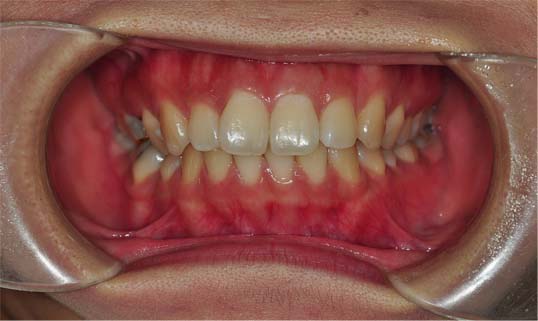

저는 치아가 덧니는 심하지 않기때문에 교정하기에 어렵지 않을거라 혼자 생각했는데 제가 잇몸과 치아 모두 돌출되어있고 어려운 케이스라고 하시더라구요 헝헝 (아래 사진을 참고해주세요~)

그중에 정말 다행인건 제 치아가 어려운 케이스이지만 개발중이이시던 나사가 이날 완성되었다고 이것으로 진행할수 있을거라고 말씀하셨는데 정말 운이 좋았던것 같아요 감사하므니다 ㅠㅠ